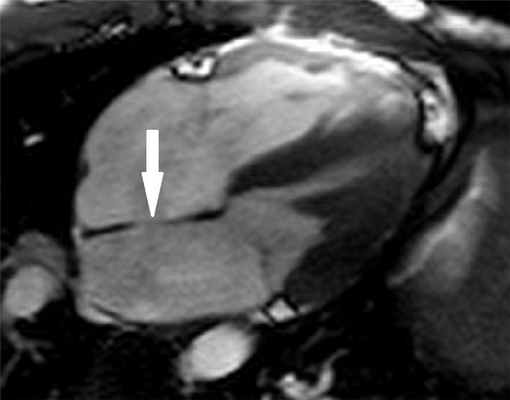

Рисунок 1. МРТ. Четырехкамерное сечение сердца. Стрелкой указан дефект межпредсердной перегородки (ДМПП).

- врожденные пороки сердца. Наиболее распространенный врожденный порок сердца - дефект межпредсердной перегородки (ДМПП). При выполнении МРТ получают изображения в различных плоскостях сердца, что позволяет отчетливо показать наличие и расположение дефекта, визуализировать турбулентный поток крови в месте дефекта. Одним из важных параметров для наличия дефекта является определение соотношения кровотока в восходящей аорте и легочном стволе (Qp/Qs). МРТ позволяет неинвазивно определить соотношение кровотоков (в норме соотношение Qp к Qs должно составлять 1).